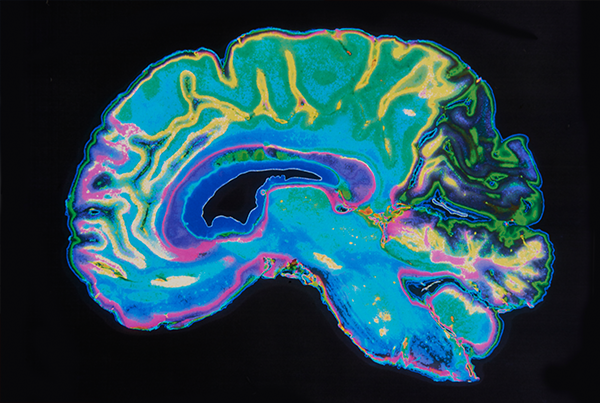

Magnetresonanztomographie (MRT), Computertomographie (CT)